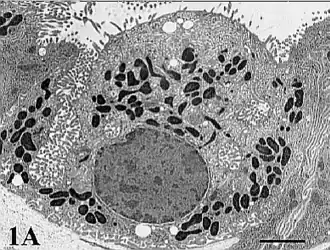

Mediante la microscopía electrónica se pueden observar las características propias de esta célula.

De forma piramidal, el citoplasma de las células parietales está repleto de mitocondrias, con abundantes lisosomas y un sistema tubulovesicular prominente.

La nanotomografía[nb 1] evidencia redes intrincadas de mitocondrias, que se distribuyen de manera uniforme por todo el citoplasma. Estos orgánulos numerosos tienen crestas compactas y una matriz densa que contiene partículas opacas.

Los lisosomas son abundantes aproximadamente esferoides, se encuentran adyacentes a las mitocondrias.

Los orgánulos de membrana tubular y vesicular (tubulovesículas) se distribuyen por todo el citoplasma de las células parietales.

La célula parietal es particularmente rica en mitocondrias; posee una de las densidades más altas de mitocondrias en el cuerpo humano, alcanza hasta el 40% del volumen total de la célula.